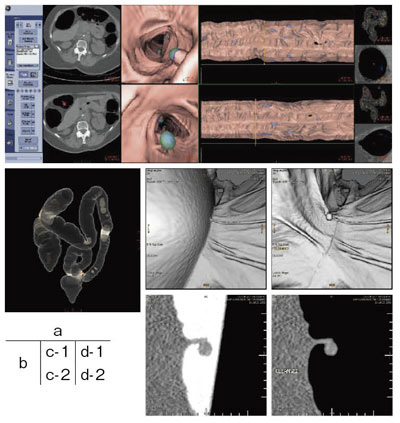

まず,アプリケーションを起動すると,空気の連続性と解剖学的位置から自動的に大腸のみを抽出し,二重造影のようなVR像や仮想内視鏡像,大腸の展開像が表示される。DCAを使用することによって,病変と予想されるような球状の構造物が青色で強調される。オペレータは,表示されたさまざまな画像から疑わしい部分にブックマークを記し,より詳細に観察することも可能である。造影剤と混合した残渣,残液を画像上でサブトラクションするElectronic Cleansingは,造影剤をあらかじめ服用するという前処置は必要なものの,患者さんの苦痛が軽減できるため,新しい前処置方法として現在多くの施設で研究,試行されている(図2)。

図2 Colon VCAR EC

a:Colon VCAR ECの全体画面(DCA On)

b:二重造影様画像

c-1:Electronic Cleansing Off仮想内視鏡像

c-2:Electronic Cleansing Offオブリーク像

d-1:Electronic Cleansing On仮想内視鏡像

d-2:Electronic Cleansing Onオブリーク像